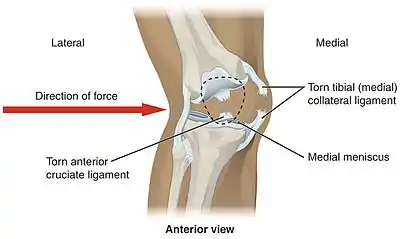

Common injuries due to physical activity

In sports that place great pressure on the knees, especially with twisting forces, it is common to tear one or more ligaments or cartilages. Some of the most common knee injuries are those to the medial side: medial knee injuries.[29]

Anterior cruciate ligament injury

The anterior cruciate ligament is the most commonly injured ligament of the knee. The injury is common during sports. Twisting of the knee is a common cause of over-stretching or tearing the ACL. When the ACL is injured a popping sound may be heard, and the leg may suddenly give out. Besides swelling and pain, walking may be painful and the knee will feel unstable. Minor tears of the anterior cruciate ligament may heal over time, but a torn ACL requires surgery. After surgery, recovery is prolonged and low impact exercises are recommended to strengthen the joint.[30]

Torn meniscus injury

The menisci act as shock absorbers and separate the two ends of bone in the knee joint. There are two menisci in the knee, the medial (inner) and the lateral (outer). When there is torn cartilage, it means that the meniscus has been injured. Meniscus tears occur during sports often when the knee is twisted. Menisci injury may be innocuous and one may be able to walk after a tear, but soon swelling and pain set in. Sometimes the knee will lock while bending. Pain often occurs when one squats. Small meniscus tears are treated conservatively but most large tears require surgery.[31]